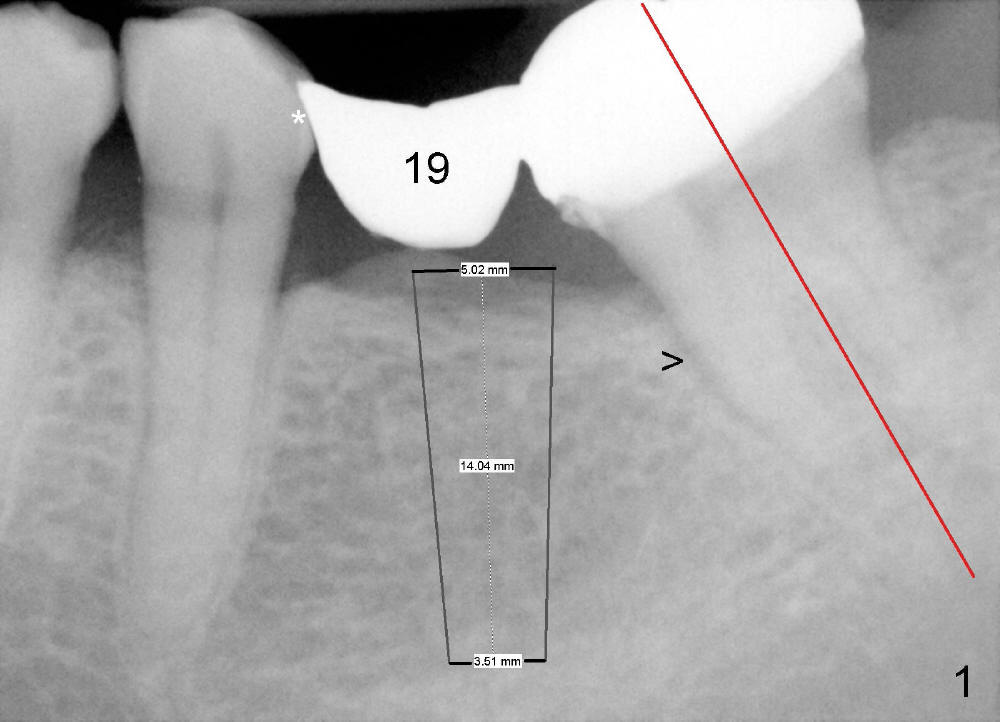

Fig.2 shows calculus in the mesial sulcus of #18 preop. After calculus removal, a 10 mm paralleling pin is inserted (Fig.3); it appears that the apical end should be moved mesially (arrow). Finally a 5x14 mm implant is placed as planned (Fig.4).